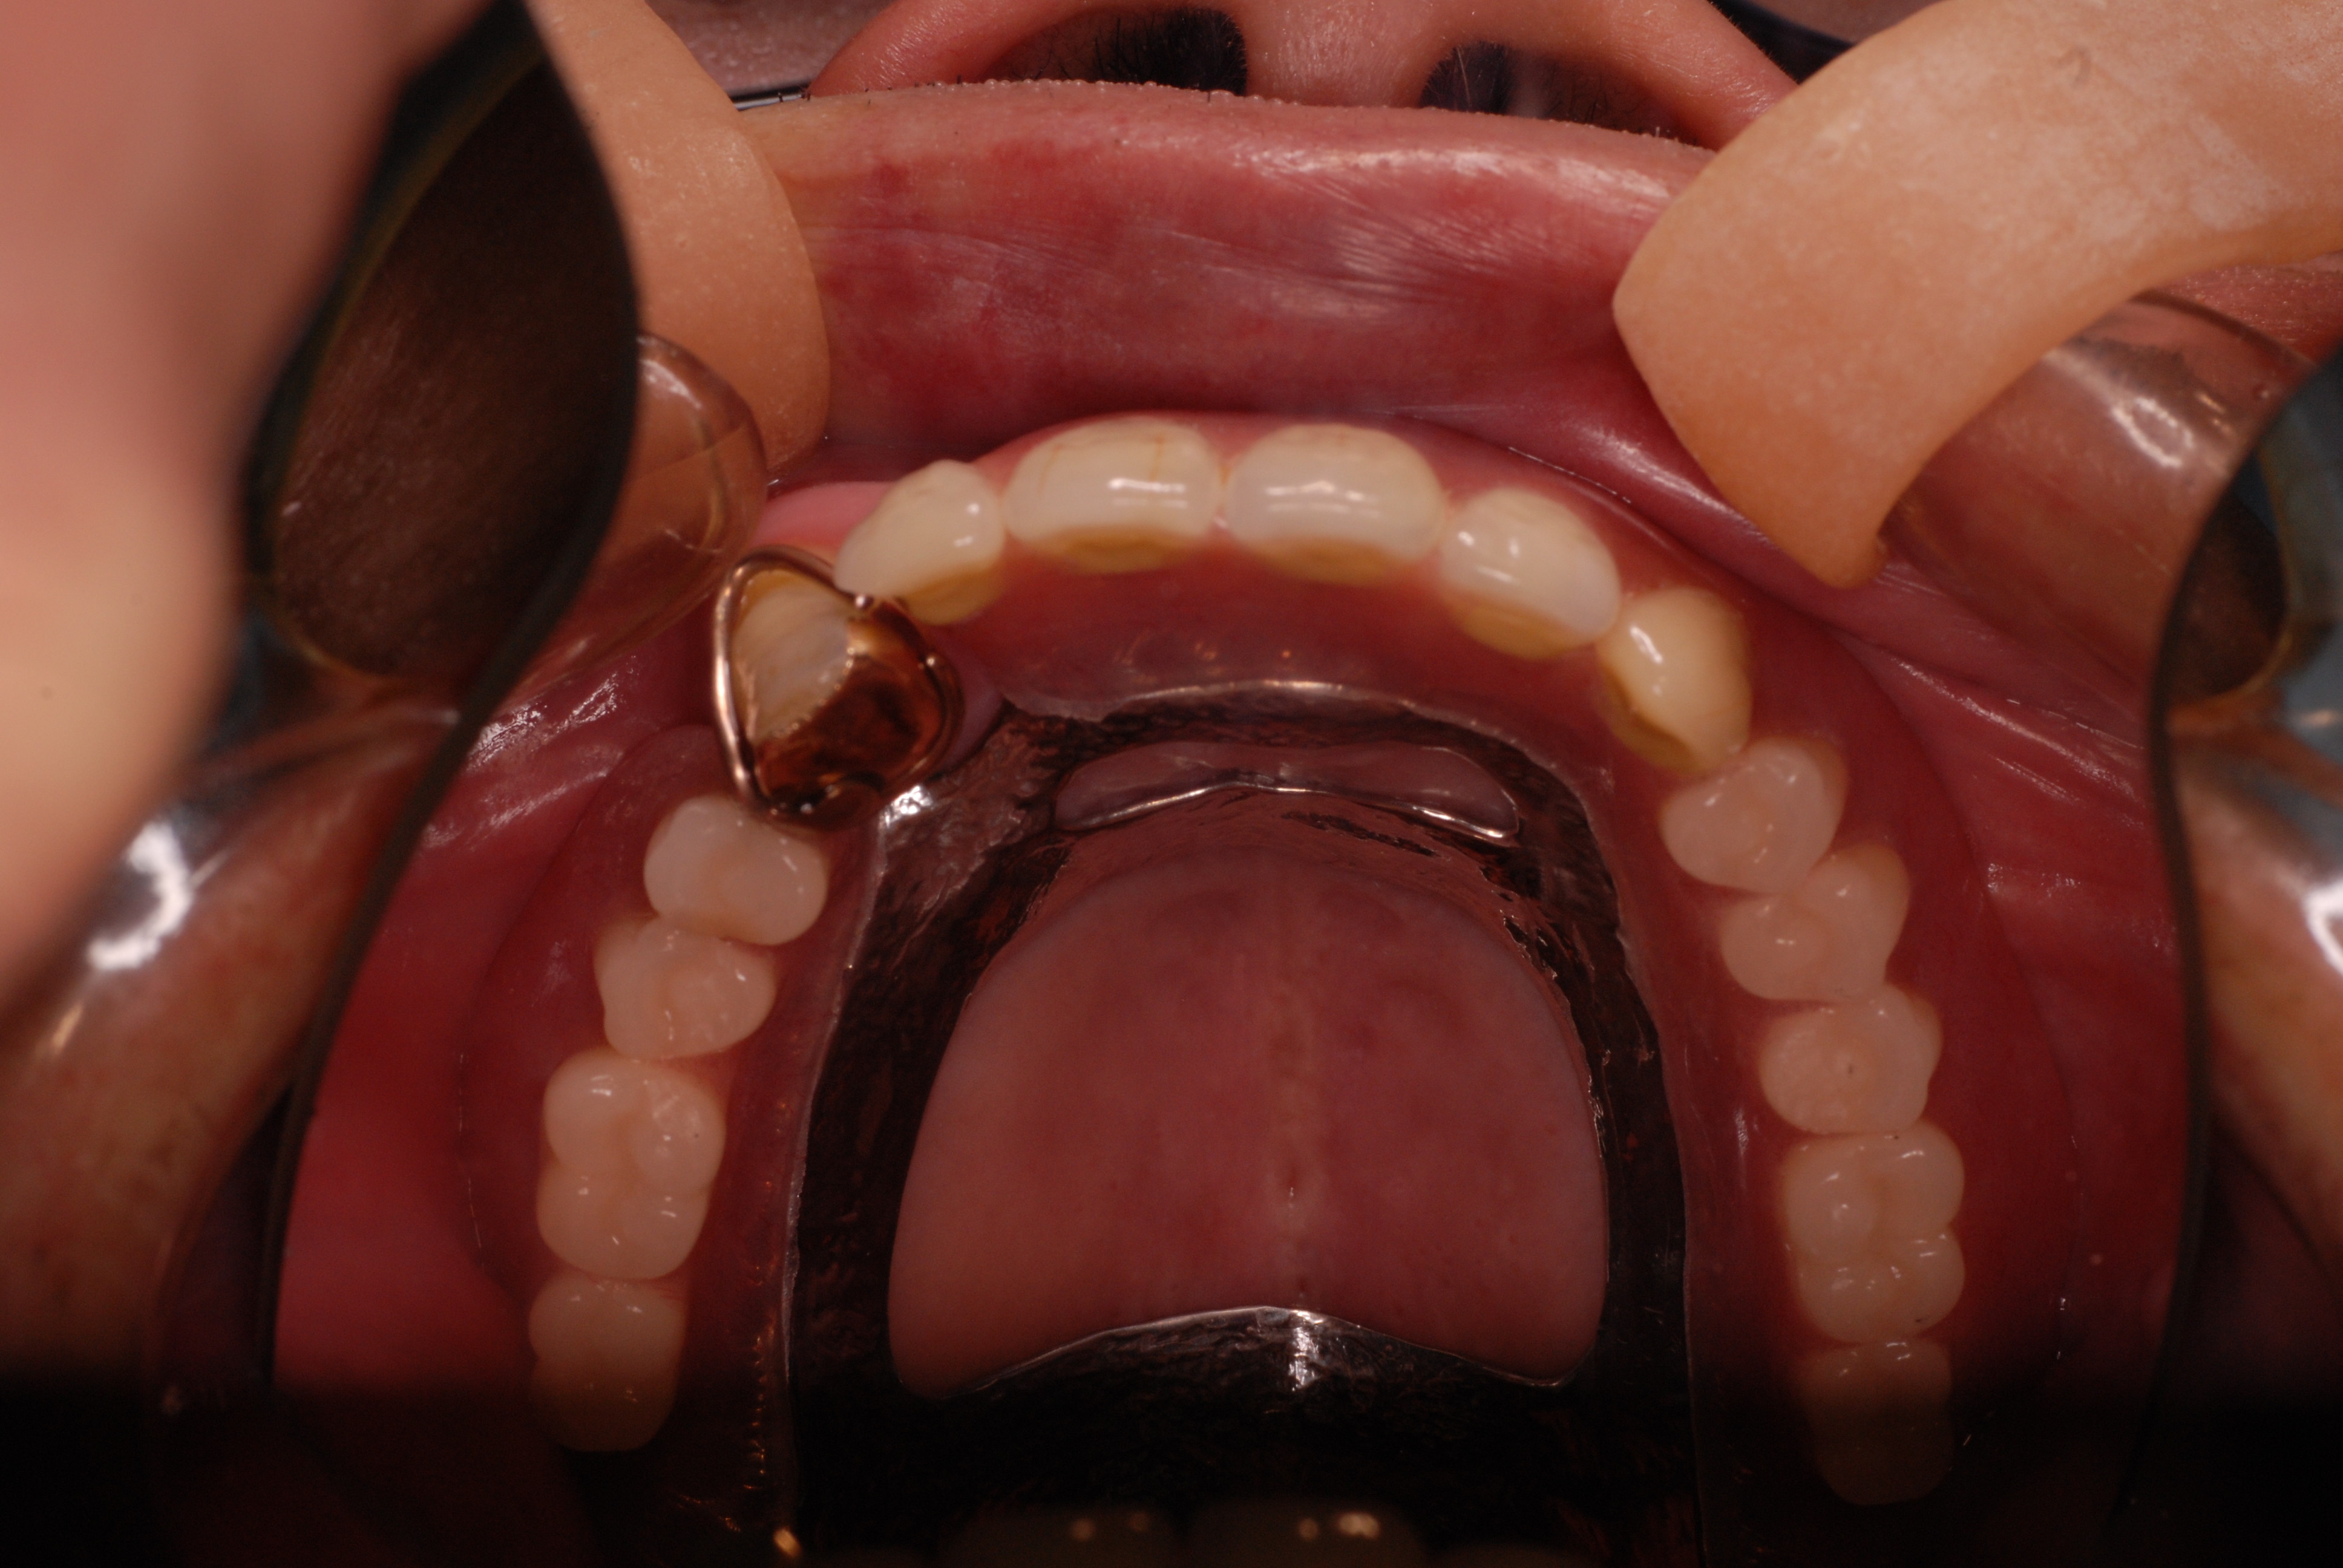

現実を見ればお口の中には“異物”である金歯、銀歯、セラミック、インプラントのオンパレードです。

これ等のものは、異物です。無い方が病気にならず健康でいられるのです。

お口の中から差し歯、入れ歯、詰め物を追放しましょう!

必ずばい菌が侵入しないようにしてばい菌である虫歯を除去します。

銀歯の下はばい菌だらけです。こういうのはよくあります。取り残しですね。![treatment_05[1]](https://livedoor.blogimg.jp/netdental/imgs/3/a/3ad019d0-s.jpg)